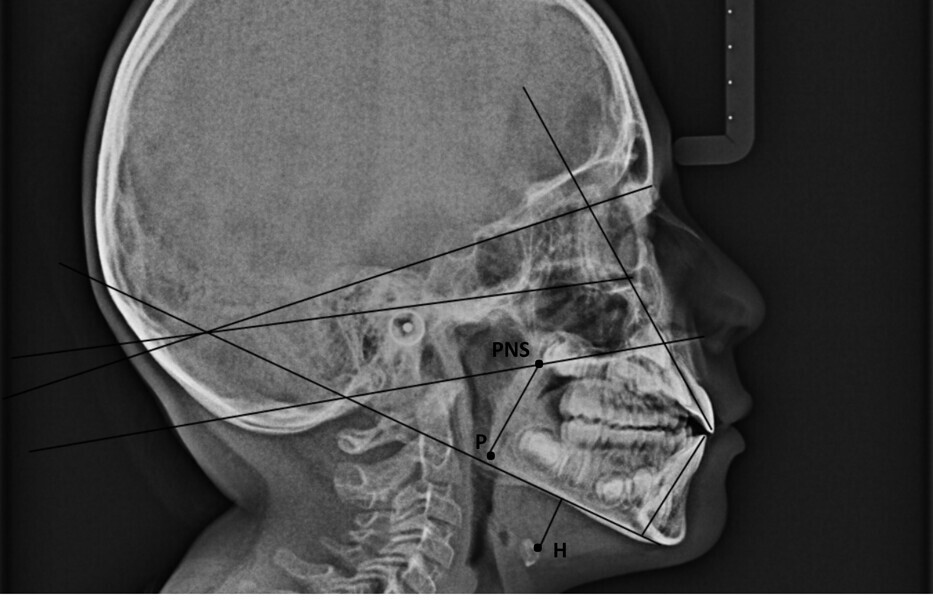

In my clinical practice, I prevent patients from rolling and rotating their heads using a cephalostat while allowing pitching: only after they have positioned themselves comfortably, do I place the post on the nasion, without exerting pressure. In this way, the patient will assume his or her habitual posture, and this too will be investigated by us. The cephalometric radiograph showed very important dysfunctional aspects (Fig. 4). Antero-rotation of the head and cervical hyper-lordosis were evident. Tracing of the tongue23 showed a very low position of the anterior part, as was found clinically. Cephalometric analysis was performed using the OrisCeph Rx1 CE program (Version 7.70; Elite Computer Italia). The patient showed a Class I skeletal pattern with antero-rotation of the maxillary plane, proclination of the mandibular incisors and increased anterior lower face height.

In the control cephalometric radiograph, the lingual position had completely regularised, the body and tip being in contact with the hard palate, creating an average overbite (Fig. 14). The cervical hyper-lordosis was moving towards correction and the skull posture was less forward.

In agreement with Yoon et al.,4 in the radiographs at T0 and T1, we also calculated the length of the soft palate because its increase in size, as far as we know, is considered a risk factor for the development of obstructive sleep apnoea, and its reduction is part of the therapeutic goals of myofunctional therapy for the treatment of obstructive sleep apnoea.28, 29 The P–PNS value had decreased from T0 (30.0 mm) to T1 (29.4 mm). Also in agreement with Yoon et al.,4 we also calculated the length of the perpendicular from the hyoid bone to the mandibular plane. An increase indicates a low tongue posture. This line had fallen from T0 (16.3 mm) to T1 (11.9 mm), giving further confirmation of improved lingual posture.